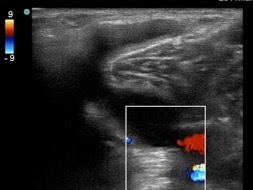

Knee Baker’s Cyst 2 Image